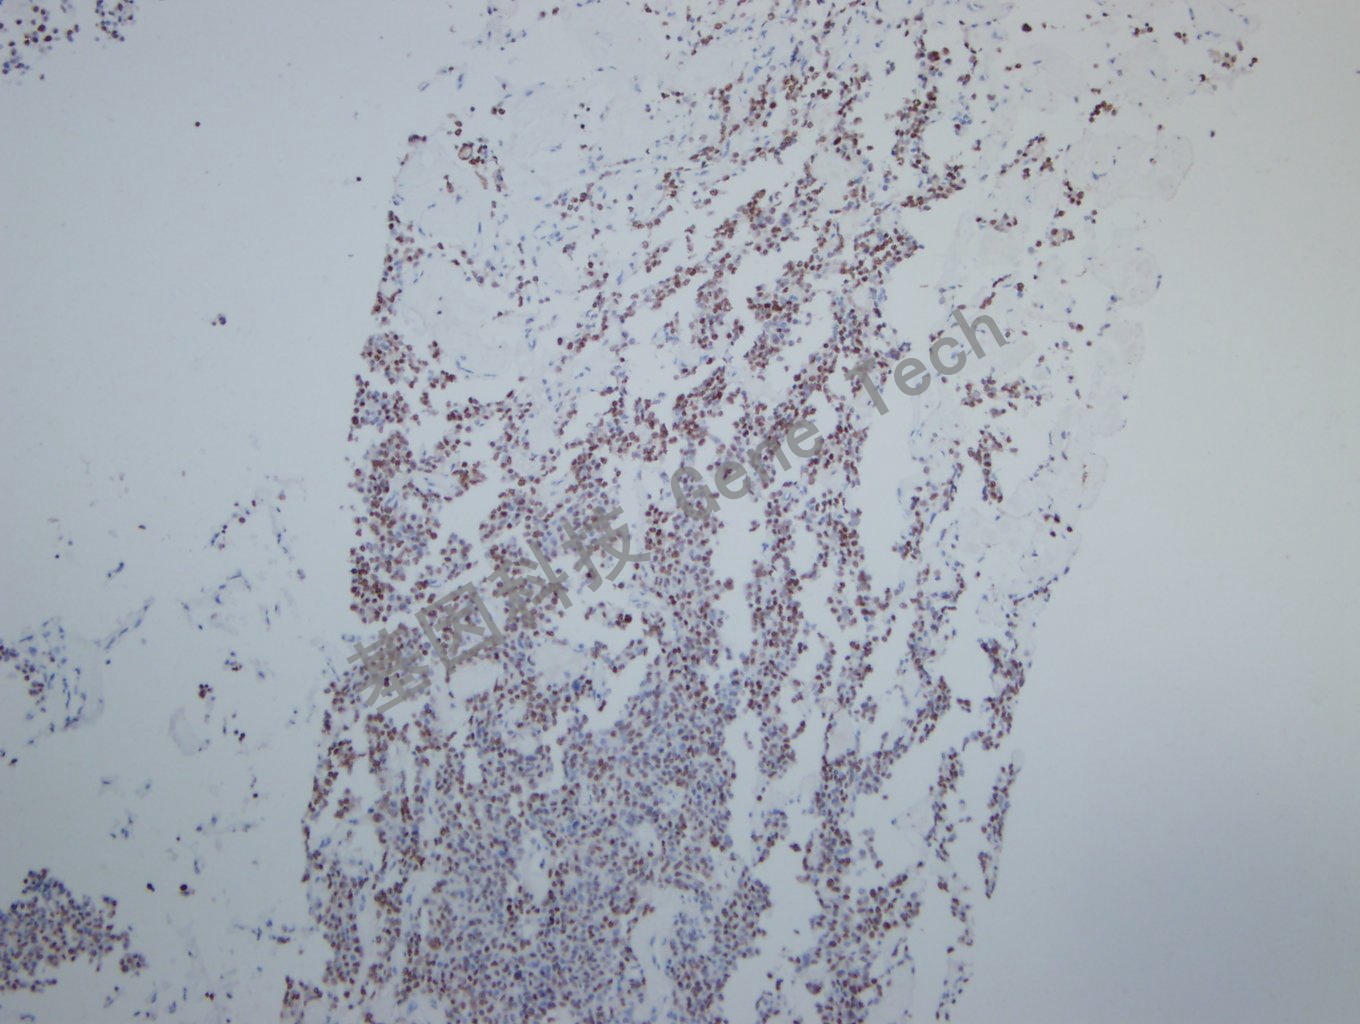

垂体瘤石蜡切片,用 PIT-1(GT2319)染色,细胞核阳性,DAB 显色。